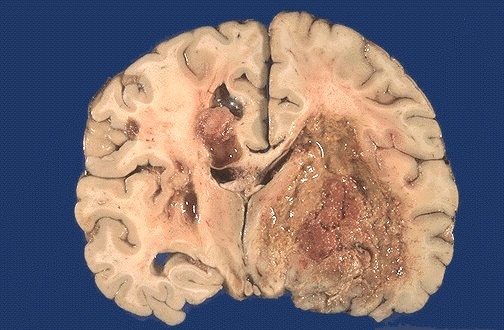

Glioblastoma gross - hemorrhage, firm white / soft yellow

Glioblastoma